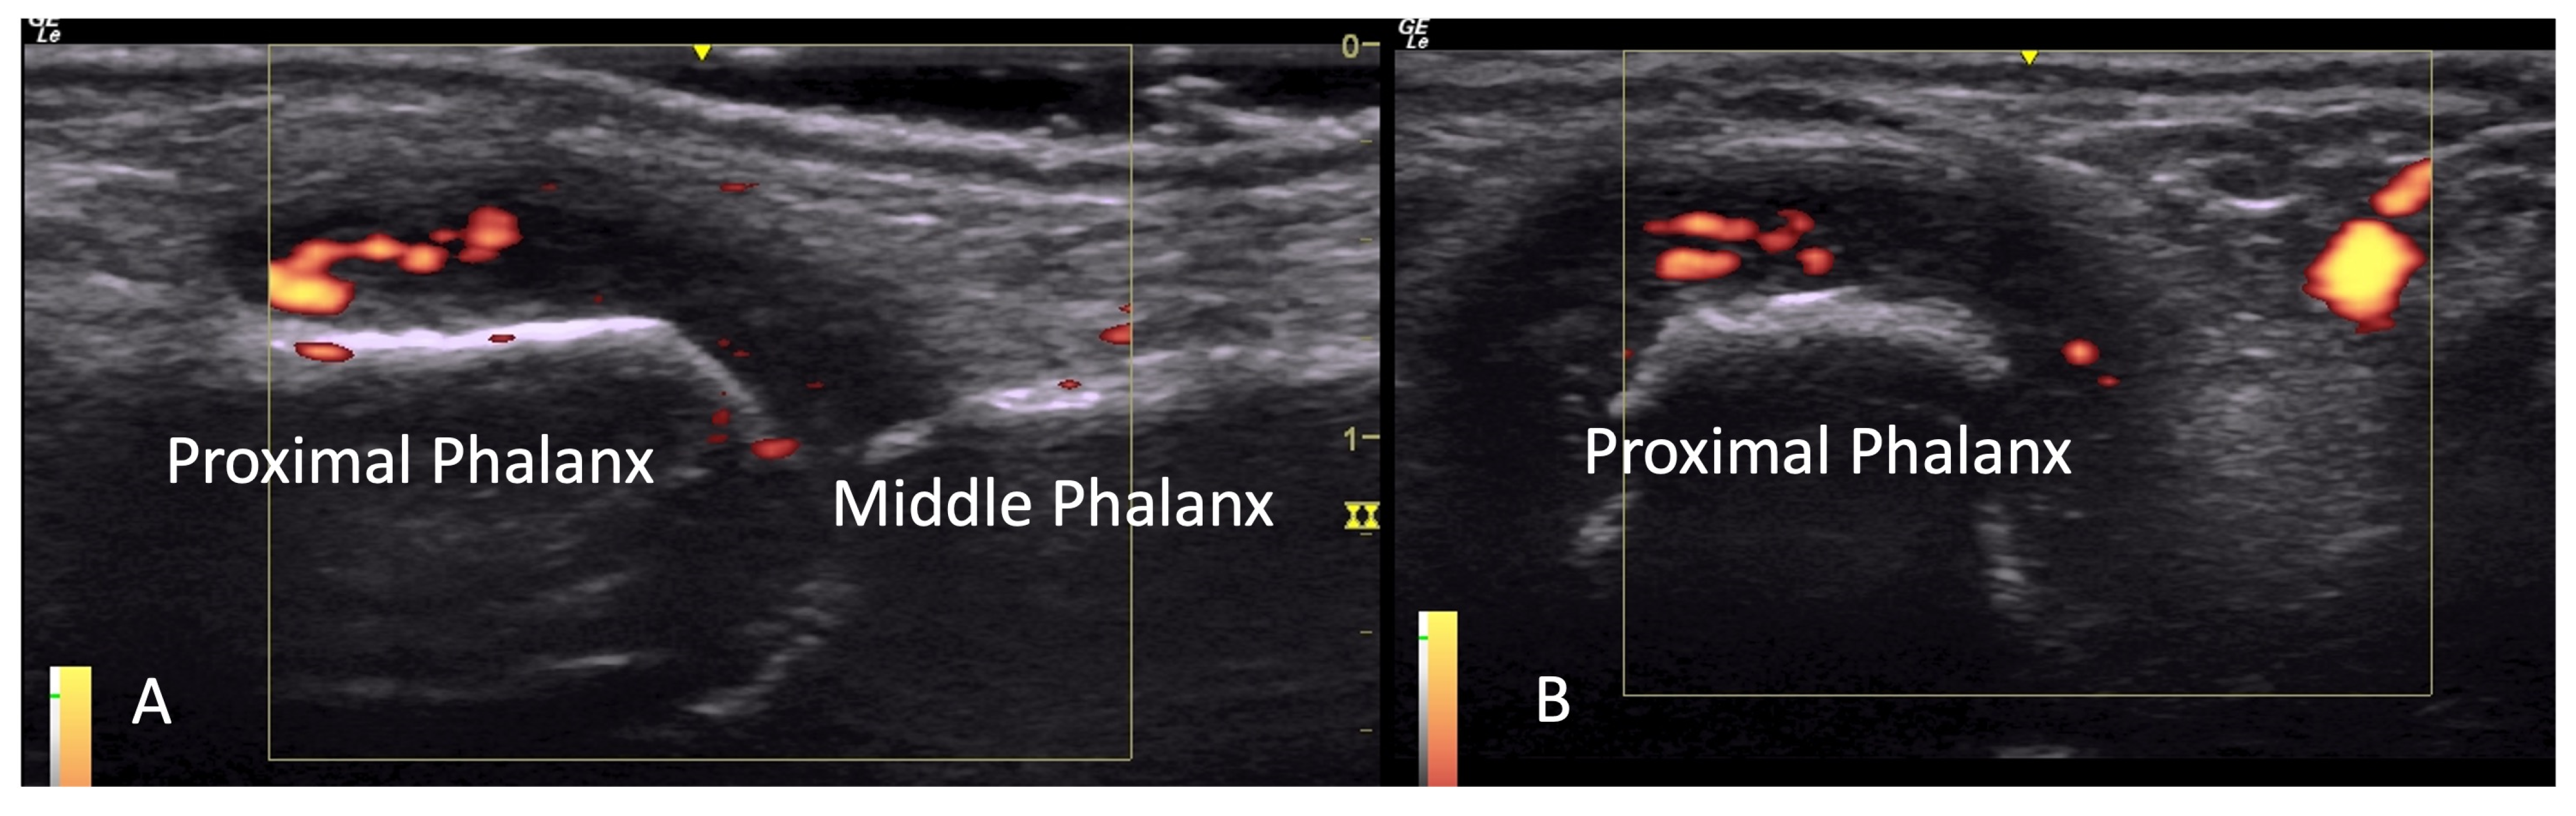

2.1. Joint Pathology

2.1.2. Inflammatory Arthritis

4.1. Evaluation of the Fingers

4.1.1. Dorsal Aspect

4.1.2. Volar Aspect